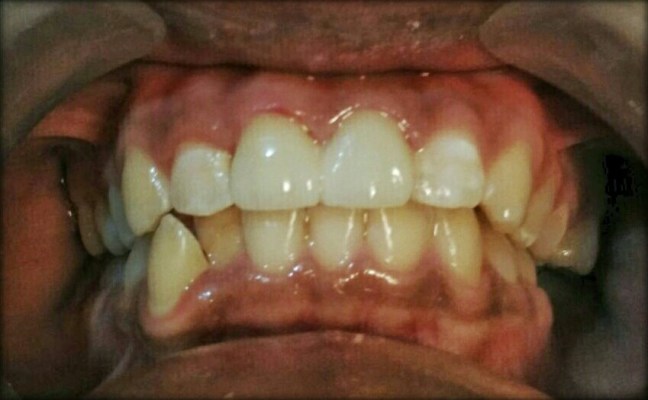

Ayo tebak gigi di atas itu gigi aselik atau palsu?

Kalau ditanyain tentu saja jawabannya adalah palsu. Hehehe.

Foto di atas merupakan kondisi gigi sebelum dilakukan tindakan. Terlihat kalau patahnya sampai kehilangan setengah dan sepertiga mahkota gigi dan sudah pasti pulpanya terbuka. Pulpa adalah bagian di dalam gigi yang terdiri dari pembuluh darah dan syaraf, jadi gak bisa asal tambal. Pulpanya harus dirawat dulu dengan perawatan syaraf atau perawatan saluran akar (PSA).

Tahap selanjutnya adalah membangun kembali inti gigi, lalu dilakukan pembentukan mahkota gigi. Setelah bentuk yang diinginkan tercapai, gigi dicetak, hasil cetakannya dikirim ke Laboratorium, pemilihan warna gigi yang paling sesuai, dan tadaaa… Gigi tampak utuh kembali. 🙂